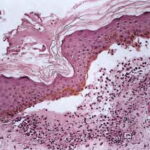

Three histologic patterns have been identified in such lesions. The first is striking basal layer vacuolization with subsequent blister formation. The second is vasculitis with subepidermal blister and pustule formation . The third and most common is a dermatitis herpetiformis-like histologic pattern. Approximately 25% of

cases are said to have a small-vessel, neutrophil-rich leukocytoclastic vasculitis beneath the blister. Histologic features more routinely identified with lupus erythematosus are not present. Another histologic finding that is not emphasized in most case reports is the presence of dermal mucin and hyaluronic acid as defined by Alcian blue stain at pH 2.5 . The frequency of mucin deposition is unknown.